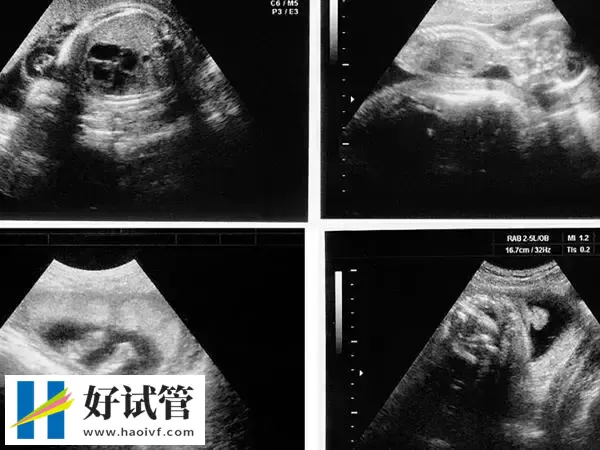

移植第38天孕囊的大小在3cm左右,此时B超下观察胎芽在1.5cm左右,因为移植38天相当于已经正常怀孕8周了,所以这个时期就不能按照孕囊大小计算了,需要按照胎芽或者头臀径计算。孕8周时胎儿长到1.66厘米,胎形已定,可分出胎头、体及四肢,胎头大于躯干。B超可见胎囊约占官腔1/2,胎儿形态及胎动清楚可见,并可看见卵黄囊。